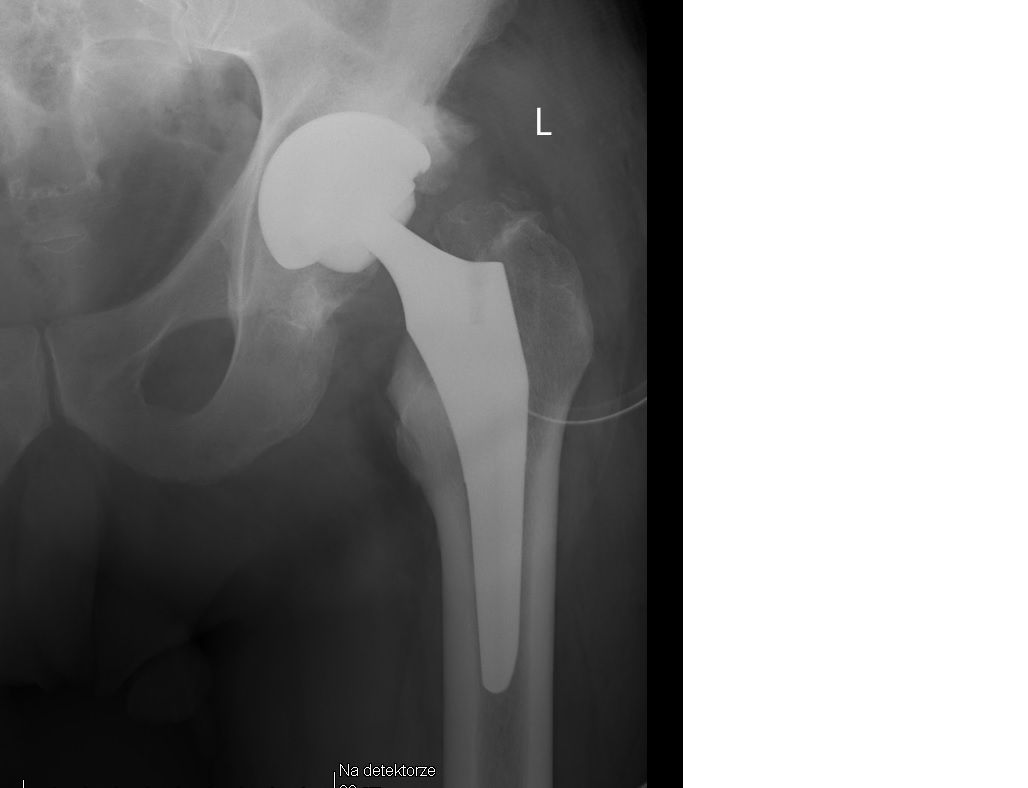

Choroba zwyrodnieniowe bioder i kolan - endoprotezoplastyki.

Zdjęcia i filmy